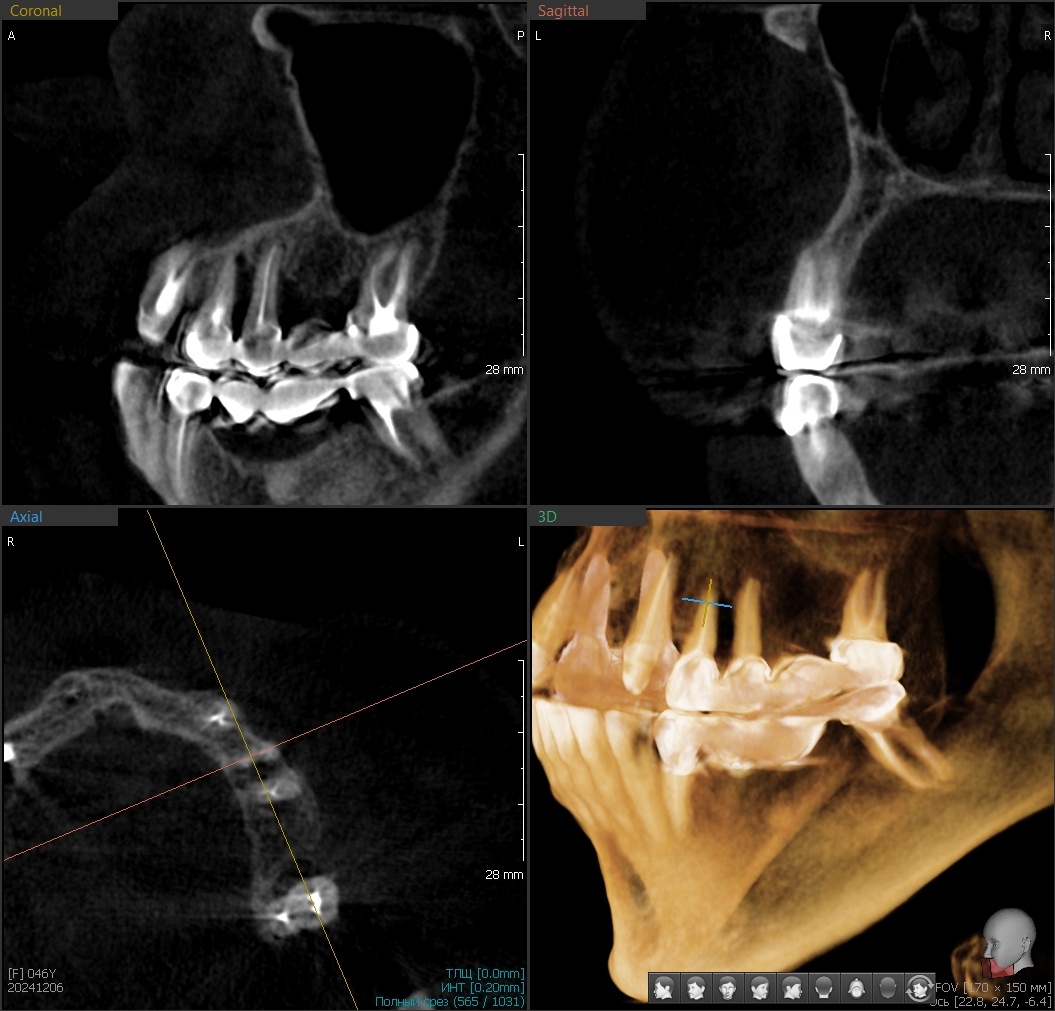

Под старыми металлокерамическими мостами зубы разрушились, кость ушла:

КТ до вмешательства

Дёсны отёчные, гиперемированные. Конструкции давно перестали выполнять свою функцию и превратились в бомбу замедленного действия.

Нужно убирать мосты, удалять зубы и начинать всё заново.